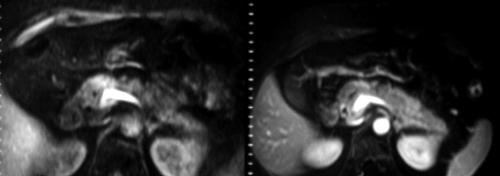

Fat suppressed breath-hold T1-weighted images and intravenous administration of Gd-DTPA are usually helpful in tumor detection since they produce an optimal contrast gradient between the neoplastic and normal parenchyma (Figure 2): according to the biphasic dynamic MR technique [5], scans performed 15 and 45 seconds (or later) after a rapid bolus injection allow optimal pancreatic enhancement.

Figure 2. Contrast enhanced MR imaging of head pancreatic neoplasm. Fat suppressed breath-hold T1-weighted MR images before and after intravenous administration of gadolinium-DTPA depict less enhancement of the tumor than that of normal pancreatic parenchyma.

The typical MR appearance of pancreatic ductal carcinomas is a mass of 3 cm showing reduced signal intensity as compared to the normal parenchyma in T1 and T1 fat-saturated images. In our experience, fat suppressed breath-hold T1-weighted sequences without intravenous contrast medium administration are able to highlight both small pancreatic solid and infiltrative neoplasms not depicted on spiral CT scans. The poor vascularization and the histological character of the neoplasm (scirrhus) are responsible for its low signal intensity and indeterminate contours. In T2-weighted images, the neoplasm may show a slight hypointense or isointense signal in cases of accompanying inflammatory parenchymal changes [3]. In gadolinium-enhanced T1 fat-saturated images, neoplasms remain hypointense in the arterial and portal images, showing progressive and gradual enhancement in the late phases: this behavior may be partially related to the accumulated contrast medium in the extracellular spaces as well as the tumoral venous abnormalities [4].